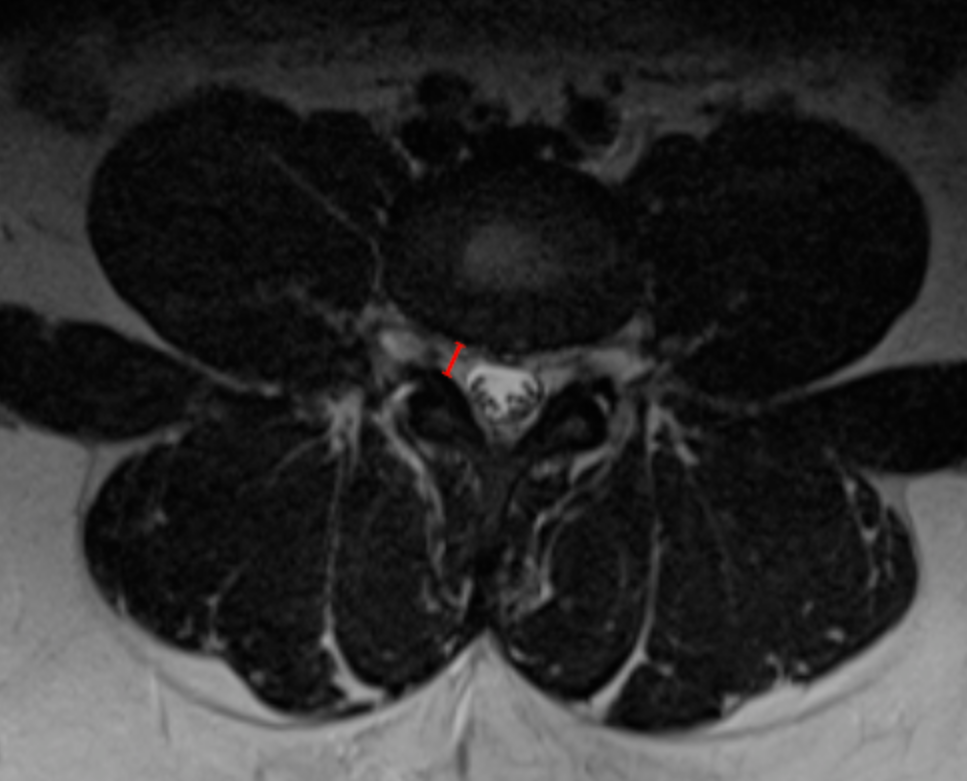

Image Type Lumbar Spine X-Ray CT Scan MRI Scan Anteroposterior (AP) Canal Diameter Cauda Equina Nerve Root Area Conus Medullaris Level Cross-Sectional Area (CSA) of Spinal Canal Disc-Height Index (DHI) Disc Herniation Size Disc Herniation Types Dural Sac CSA Epidural Fat Thickness Filum Terminale Thickness Foraminal Height and Width High-intensity Zone (HIZ) Lateral Recess Width/Depth Modic Endplate Changes (Type I, II, III) Modic (Marrow Signal) Changes Pfirrmann Classification (I-V) Vertebral Bone Quality (VBQ) Score Vertebral Endplate Defects